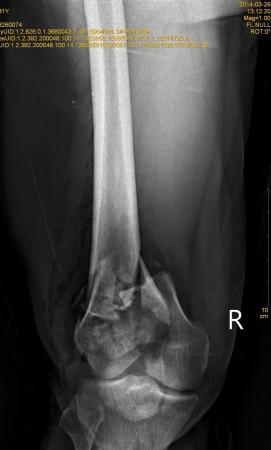

右股骨远端开放性粉碎性骨折

患者XXX,男,31岁,农民。高空跌伤致右大腿畸形伴活动性出血1小时入院。患者一般情况可,体重80kg。完善相关辅检,入院诊断:1.右股骨远端开放性粉碎性骨折;2.右髌骨粉碎性骨折;3.右桡骨远端骨折。入院后行右股骨开放性骨折清创缝合术+右胫骨结节骨牵引术,布朗支架抬高制动,目前患者右大腿远端肿胀明显,给予抗感染,消肿止痛等对症支持治疗。 2014-3-19,爱爱医***里mimi98发了类似的帖子,我刚好也遇到了同样的病例,诚心向各位老师、战友寻求好的治疗方案。